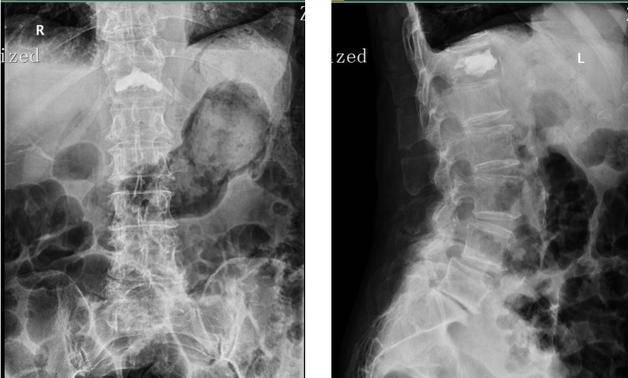

类风湿患者为何会骨质疏松?许多类风湿病患者在来医院接受治疗时被诊断出患有骨质疏松症,这使得治疗更加复杂。他们想知道,他们并不老,如何得骨质疏松症? 类风湿和骨质疏松如影随形 多年的临床实践和科学研究证实,类风湿病患者骨质疏松甚至脆性骨折的发病率明显高于正常群体。 由于类风湿继发性骨质疏...